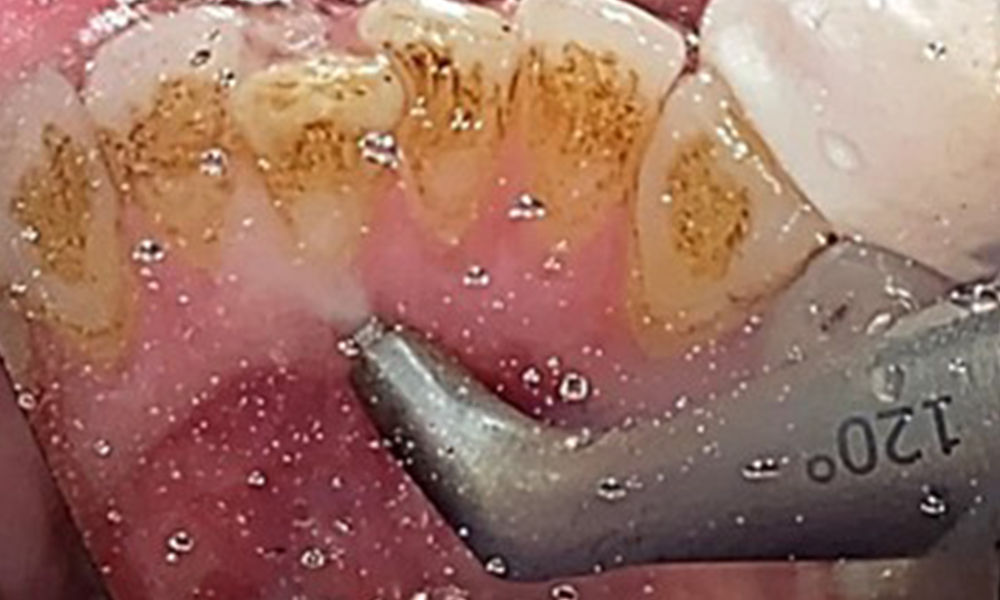

Ziel ist es durch supra- und subgingivale Biofilmentfernung das Erkrankungsrisiko zu kontrollieren. Die Wahl der Instrumente erfolgt

bedarfsgerecht. Zunächst sind Zahnstein und ggf. Konkremente mit Ultraschall und / oder Handinstrumenten zu entfernen (Abb. 10).